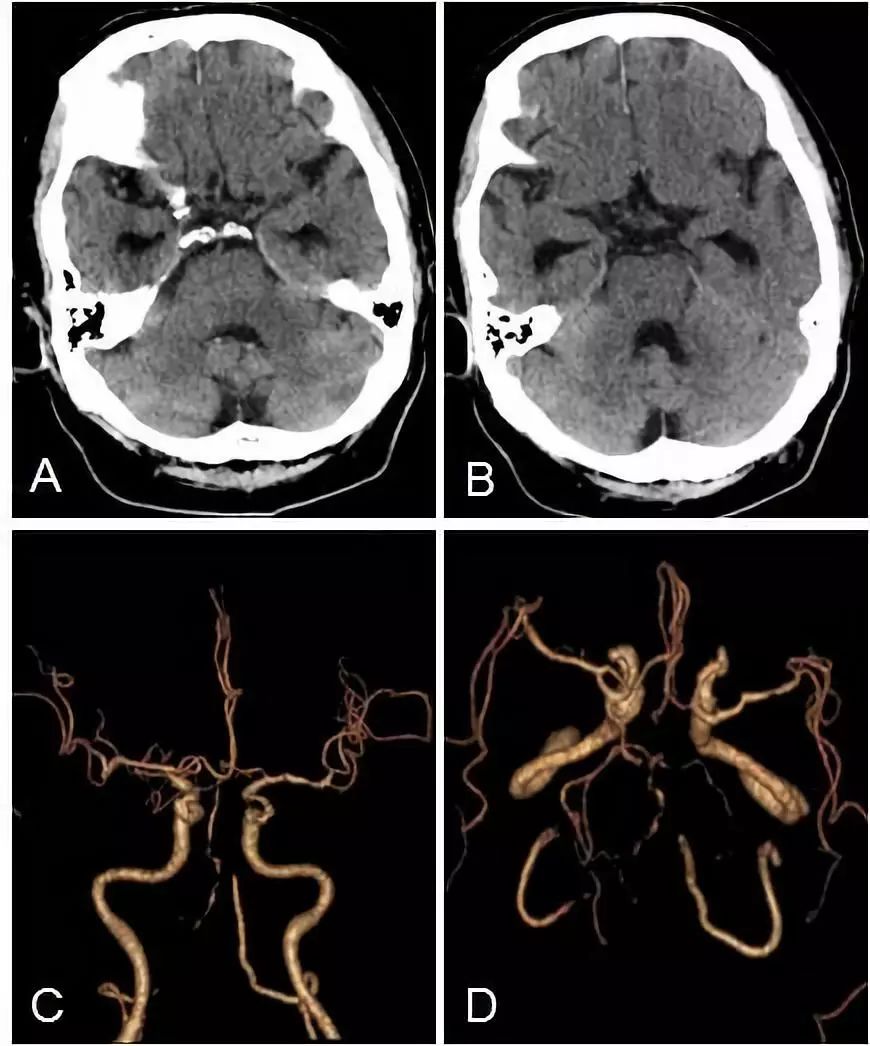

头颅CT+CTA:脑干及小脑半球多发梗死(图3A,B),双椎动脉V4段闭塞,基底动脉近段重度狭窄(图3C,D)。

图3

DSA(2019-09-06):右大脑后动脉为胚胎型大脑后动脉,右大脑后动脉P1段发育缺如,未见基底动脉尖显影(图4A,B);左后交通动脉发育不良,双小脑上动脉逆向显影(图4C,D);右锁骨下动脉开口处中度狭窄,右侧椎动脉自V3-V4移行处闭塞,右椎动脉V3段穿支与右小脑后下动脉吻合,向基底动脉供血,可见基底动脉管腔粗细不均,右小脑后下动脉起始处狭窄(图4E,F)。左椎动脉造影示左椎动脉发出小脑后下动脉以远闭塞,通过脊髓前动脉及小脑后下动脉分支与基底动脉吻合向基底动脉代偿供血,基底动脉显影欠佳(图4G,H)。

图4